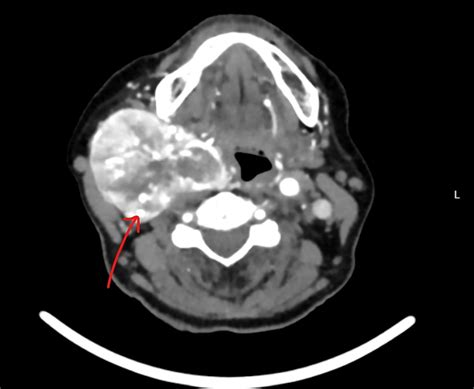

Diagnosing a Carotid Body Tumor requires a combination of physical examination and advanced imaging studies. When a physician suspects such a growth, they typically use specific diagnostic tools to differentiate it from enlarged lymph nodes or other neck masses. The “Lyre sign,” seen on imaging, is a classic finding where the internal and external carotid arteries are splayed apart by the tumor mass.

CT Angiography (CTA) Provides detailed views of the tumor's size and its relationship to major arteries.